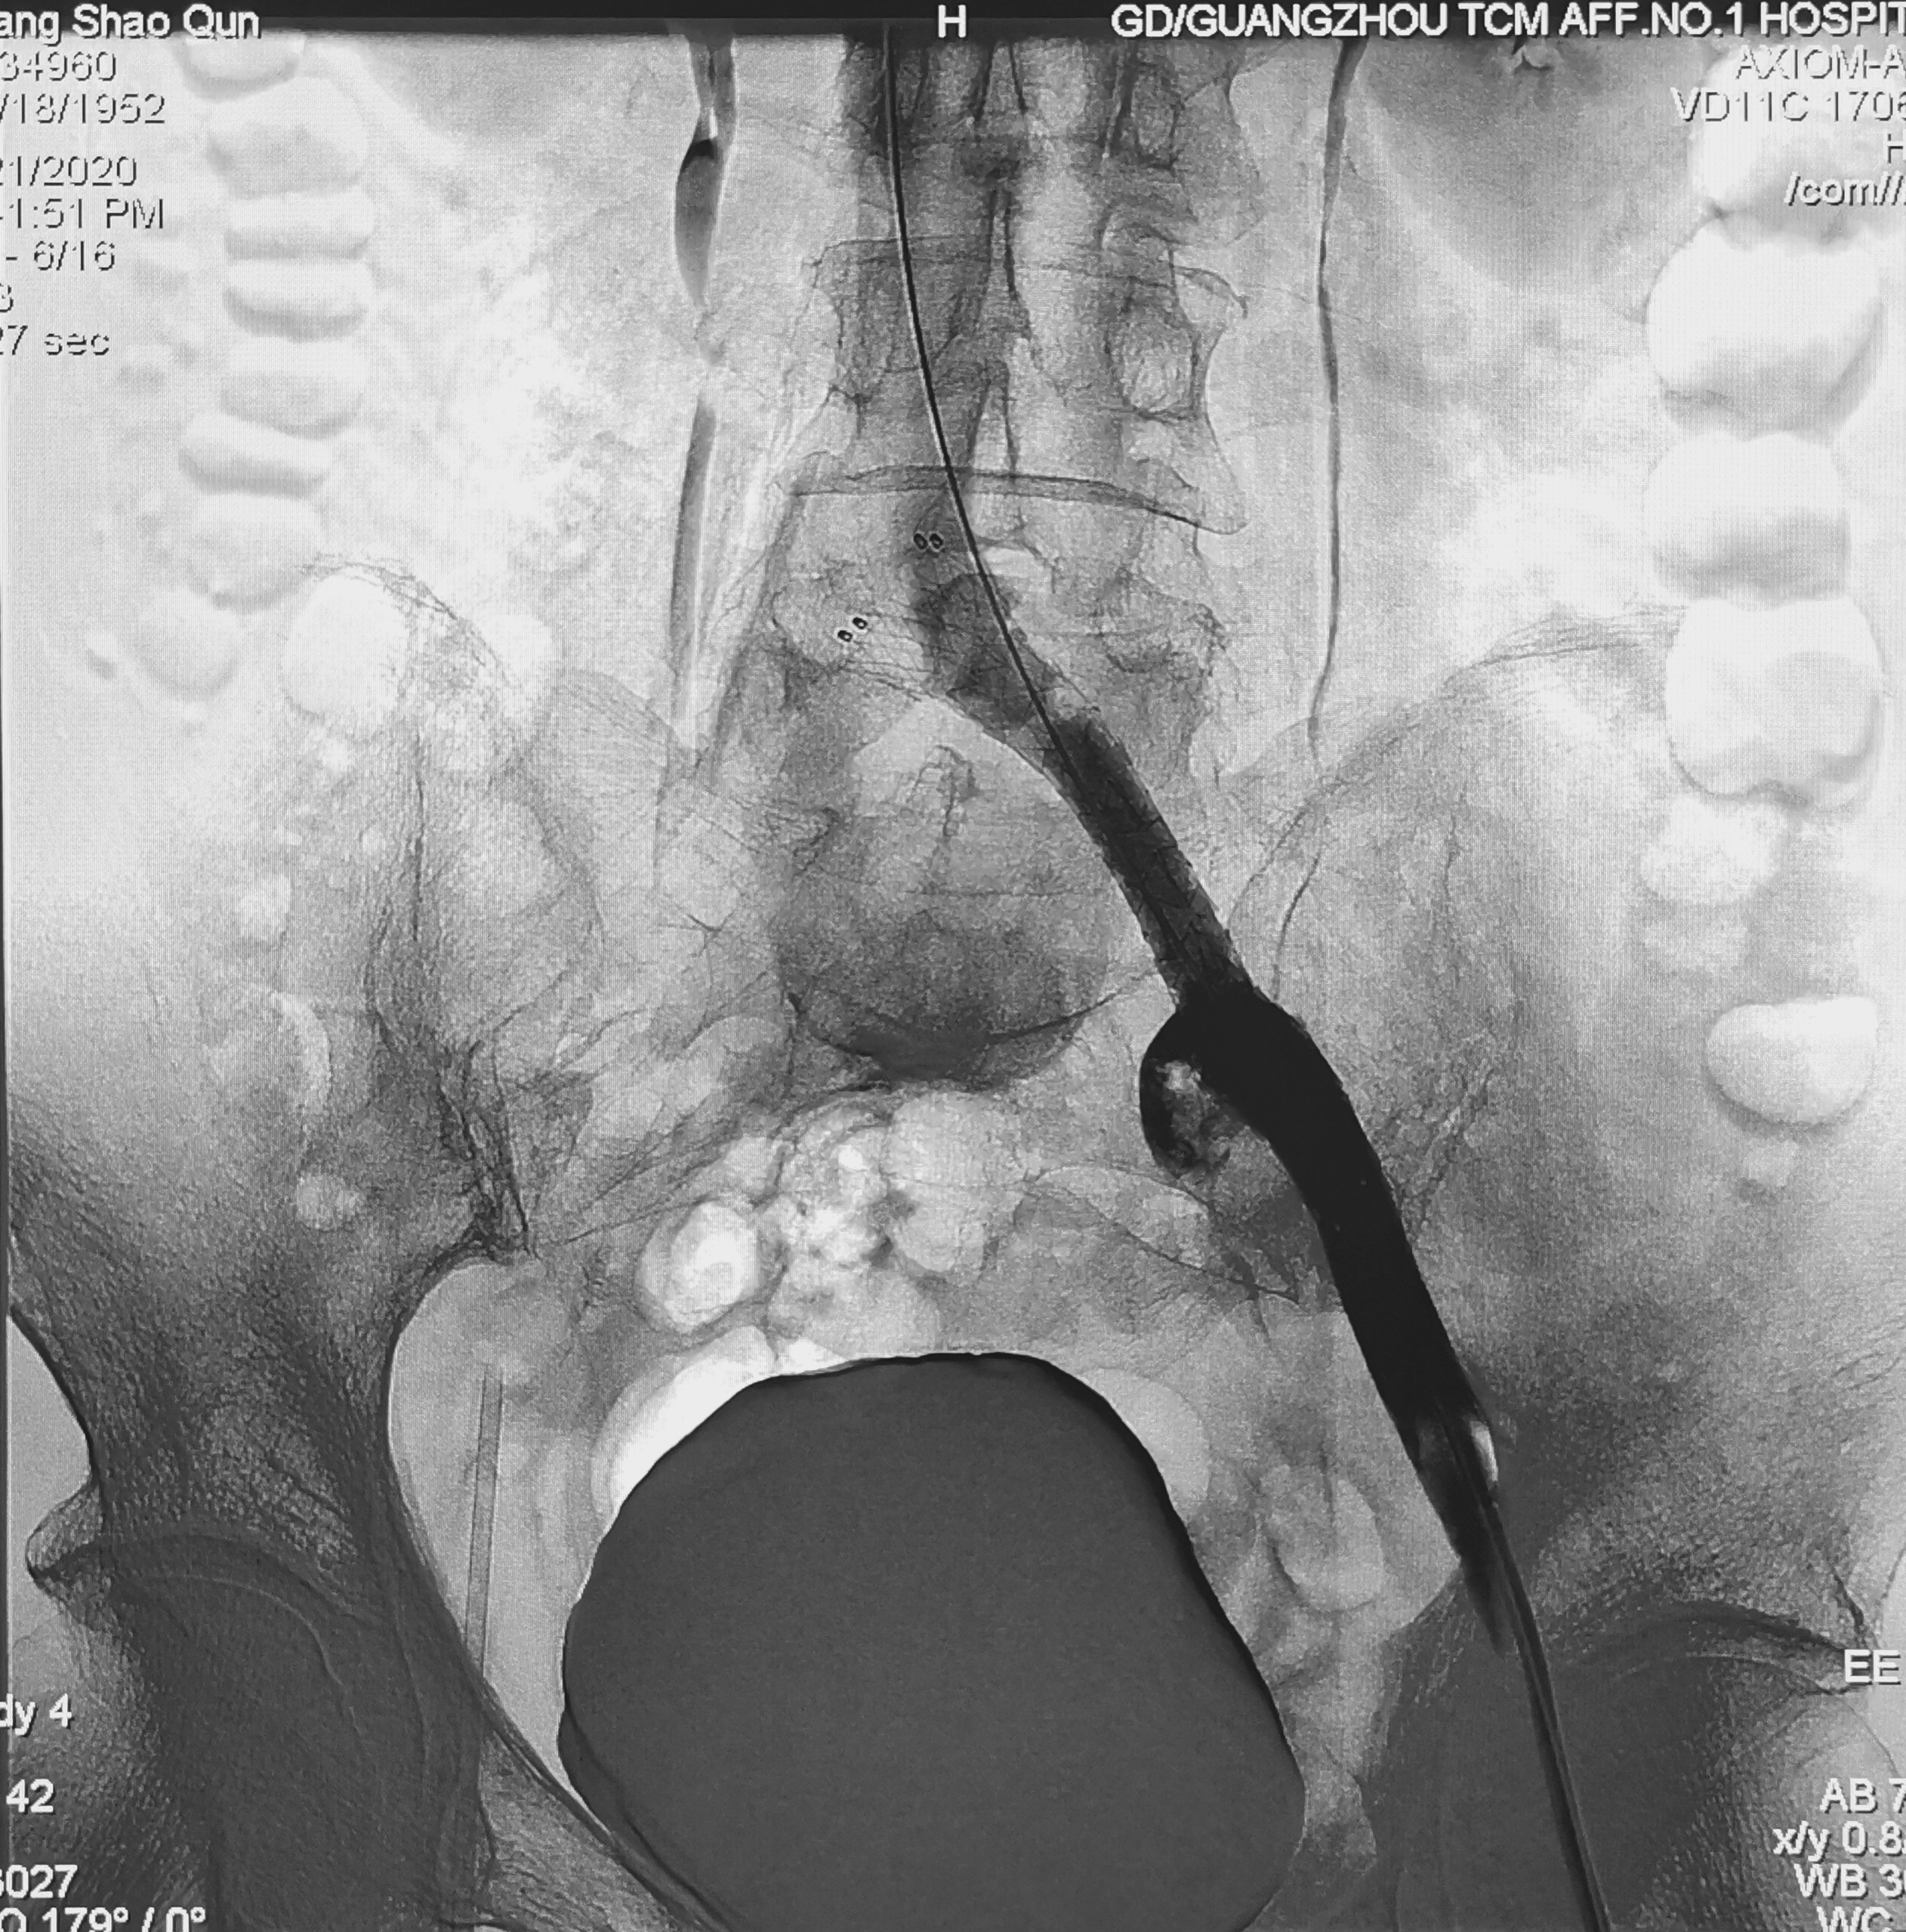

左髂股静脉血栓,正在插管清除

然而,有的病人很困惑,才在医院清除血栓,转眼间下肢又肿起来,检查发现还是血栓,这可怎么办呢?